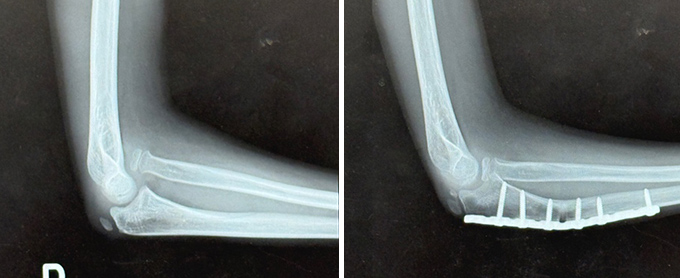

上腕骨遠位端骨折

肘を構成する上腕骨の末端が折れる外傷で、転倒や交通事故などで強い衝撃が加わって発生します。関節面のずれや骨片の転位を伴うと、肘の安定性と可動域が大きく損なわれます。治療の基本は、プレートやスクリューによる解剖学的整復と強固な固定であり、手術後は早期からリハビリを開始して肘の動きを保つことが極めて重要です。高齢者では骨の脆弱性や全身状態に応じて、保存加療や人工関節置換術を選択することもあります。

症例 50代 女性

(術前)

(術後 12か月)